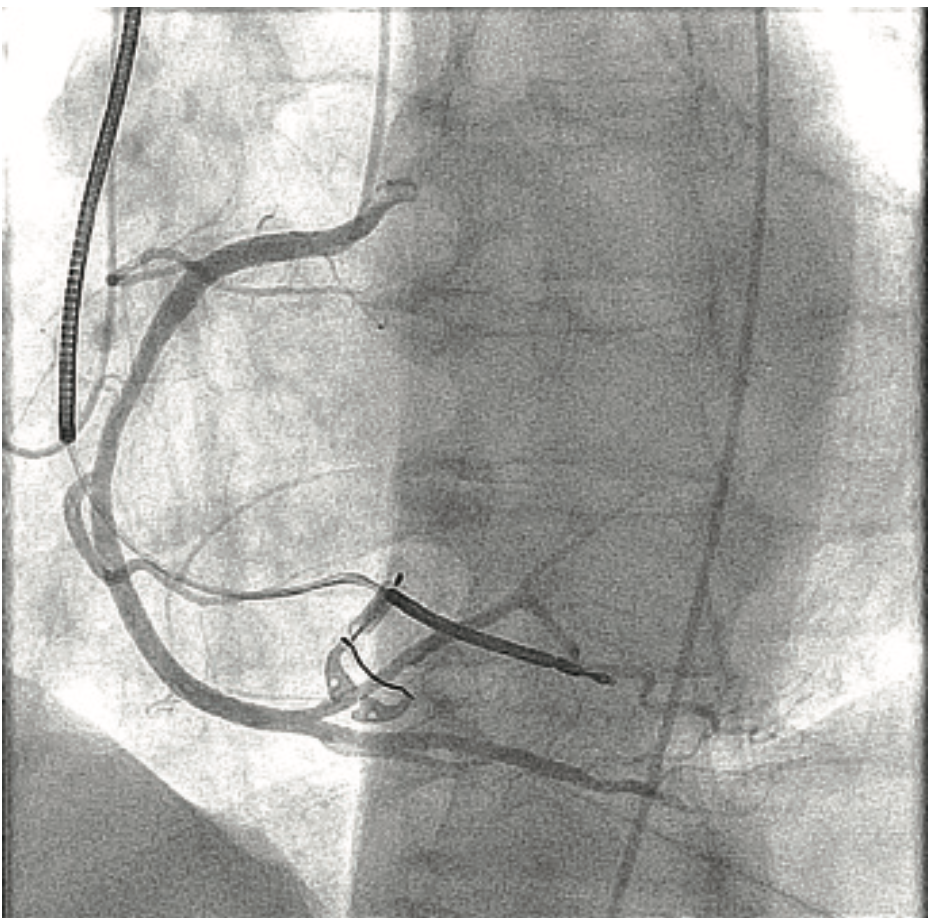

Can you give us some additional background on the case you share (sidebar)?

This is a 79-year-old woman with emphysema, arthritis, and severe aortic stenosis, and she needed a TAVR. There were several issues with her TAVR: one was that her coronary heights were low. If you put a TAVR valve in a patient with very low coronary heights, there is a chance that the native valve will get pushed up and occlude the coronary artery. We’ve had that happen once before, and the patient died from it, so it is a very serious complication. We did a novel procedure called the bioprosthetic aortic scallop intentional laceration to prevent iatrogenic coronary artery obstruction (BASILICA) procedure, where you slice the leaflet of the native aortic valve in half. Even though the leaflet gets pushed up, since it has been sliced in half, it won’t occlude the coronary artery. We first needed to look at her coronary arteries and the cusps using 3-6 cc coronary injections, and then we performed the BASILICA procedure. The patient also had an anomalous takeoff of her carotid arteries. We wanted to use a carotid embolic protection device, but because she had such an anomalous takeoff, it had to be placed in a very unique way. We did have a CT scan and had to correlate it with the patient so we would know exactly where to put the device. We needed to take an arch angiogram, which is a higher power contrast injection, 10 for 15 ccs or 10 for 20 ccs. The TAVR procedure was done as usual, using the 10 cc contrast injection I described earlier, to measure the annulus planes and look at implant depth. Then we looked at the coronary arteries, because it turned out that the patient needed a stent in her coronary artery. At the end of the case, we wanted to make sure that our closure of the large-bore access sheath was sufficient, so we flipped down to the leg and took a picture there using digital subtraction angiography and a 2 cc injection. I’ll share a second case that also demonstrates the versatility of the ACIST (Images 2-6). This was a patient with acute shortness of breath and chest pain, and there was a question of whether he was having a pulmonary embolus or a heart attack. The electrocardiogram was unclear. We took him back to the lab and were able to do a pulmonary angiogram, then visualize the coronaries, all on one setting. We also did an iliac angiogram, because we used that access in order to give him a support device. This case required pulmonary (Images 2-3), coronary (Images 4-5), and iliac angiograms (Image 6), all done with use of the ACIST CVi system.